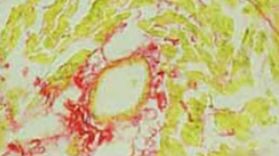

The objective of our study was to investigate the effect of Aliskiren, a renin inhibitor, on the deoxycorticosterone (DOCA) induced myocardial fibrosis in a rat model and its underlying mechanism. A total of 45 Sprague-Dawley (SD) rats underwent right nephrectomy and were randomly assigned into 3 groups: control group (CON group: silicone tube was embedded subcutaneously); DOCA treated group (DOC group: 200 mg of DOCA was subcutaneously administered); DOCA and Aliskiren (ALI) treated group (ALI group: 200 mg of DOCA and 50 mg/kg/d ALI were subcutaneously and intragastrically given, respectively). Treatment was done for 4 weeks. Sirius red staining was employed to detect the expression of myocardial collagen, and the myocardial collagen volume fraction (CVF) and perivascular collagen volume area (PVCA) were calculated. Radioimmunoassay was carried out to measure the renin activity (RA) and content of angiotensin II (Ang II) in the plasma and ventricle. Western blot assay was done to detect the expressions of extracellular signal-regulated kinase 1/2 (ERK1/2), phosphorylated ERK1/2 (PERK1/2) and matrix metalloproteinase 9 (MMP-9). In the DOC group and ALI group, the CVF and PVCA were significantly increased; the RA and Ang II levels in the plasma and ventricle were remarkably lowered when compared with the CON group. The RA and Ang II levels in the ventricle of the ALI group were significantly lower than those in the DOC group. Moreover, the expressions of ERK1/2, PERK1/2 and MMP9 were the lowest in the CON group, but those in the ALI group were significantly reduced as compared to the DOC group. ALI can inhibit the DOCA induced myocardial fibrosis independent of its pressure-lowing effect, which may be related to the suppression of RA and Ang II production, inhibition of ERK1/2 phosphorylation and MMP9 expression in the heart.